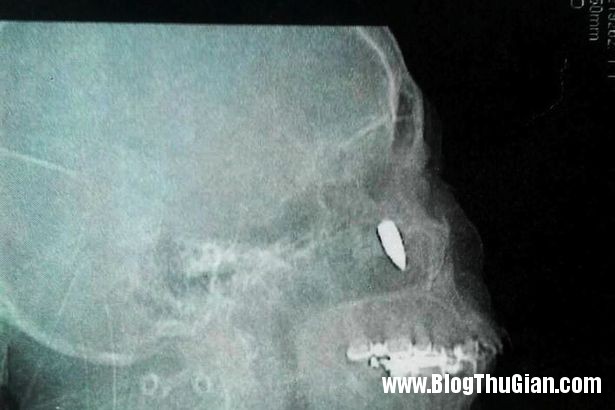

Vị trí viên đạn “ẩn náu” suốt gần nửa thế kỷ trên mặt bà Zhao. Ảnh: Want China Times.

Các bác sĩ kiểm tra và phát hiện viên đạn dài 2,5 cm trong hốc mũi của người phụ nữ 62 tuổi. Chia sẻ sau ca phẫu thuật, bà Zhao cho biết: “Tôi mừng vì viên đạn không giết chết tôi. Thật may mắn, tôi vẫn còn sống và tận hưởng những ngày tháng bên gia đình”. Sự việc kì lạ này khiến nhiều người ngạc nhiên. Họ không thể giải thích việc tại sao viên đạn có thể nằm dưới hốc mũi và tại sao người phụ nữ ấy có thể sống chung với nó suốt gần nửa thế kỷ mà không hề hay biết. Zhao kể rằng một vật gì đó từng đập mạnh vào phần mặt bên phải khi bà 14 tuổi. Lúc đấy, bà nghĩ vật đó là một viên đá nhưng thực chất nó là một viên đạn lạc. Như vậy, viên đạn đã “trú ẩn” trong mũi bà suốt 48 năm.